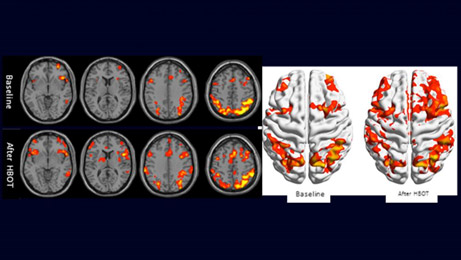

Ejemplo clínico de imágenes cerebrales funcionales por fMRI. La actividad cerebral reducida en los lóbulos frontales del cerebro y en el hipocampo mejora después de la terapia de oxígeno hiperbárico. Foto: Centro Médico Shamir

“El oxígeno es la fuente básica de producción de energía. Necesitamos oxígeno para generar energía. Generalmente, el cerebro no funciona al 100 por ciento cuando le falta oxígeno. Tenemos dos vasos principales que llevan sangre al cerebro y solo ciertas partes del cerebro están activas cuando no tenemos suficiente energía para el resto. Entonces, estas regiones cerebrales hipometabolizadas no pueden sanar si no tienen suficiente energía”, dice la Dra. Doenyas-Barak, comparándolo con alguien que pone una almohada contra la cara de alguien para que no pueda respirar, señalando la necesidad de una respuesta curativa. “También pudimos demostrar cambios en la actividad de ciertas regiones del cerebro, como la corteza prefrontal y el hipocampo, y una mejor conectividad. Hubo una muy buena correlación entre los cambios en la puntuación clínica [de nuestros pacientes] y la actividad en ciertas regiones del cerebro”.